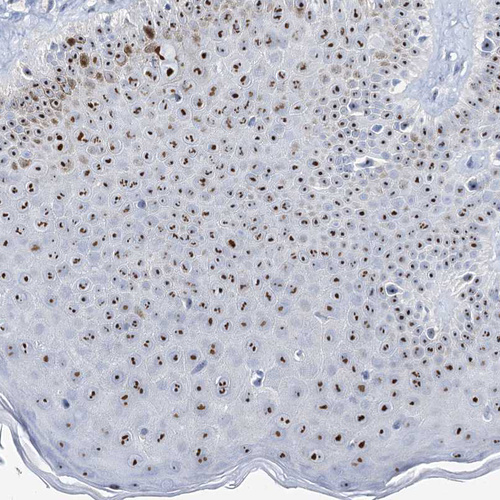

Immunohistochemical staining of human skin shows strong positivity in nucleoli in squamous epithelial cells.